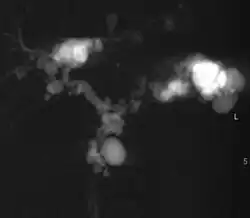

| Turbo spin echo T2-weighted axial MRI of Caroli disease, showing cystic dilatations of bile ducts (shown as white).[1] | |

Modern imaging techniques allow the diagnosis to be made more easily and without invasive imaging of the biliary tree.[9] Commonly, the disease is limited to the left lobe of the liver. Images taken by CT scan, X-ray, or MRI show enlarged intrahepatic (in the liver) bile ducts due to ectasia. Using an ultrasound, tubular dilation of the bile ducts can be seen. On a CT scan, Caroli disease can be observed by noting the many fluid-filled, tubular structures extending to the liver.[4] A high-contrast CT must be used to distinguish the difference between stones and widened ducts. Bowel gas and digestive habits make it difficult to obtain a clear sonogram, so a CT scan is a good substitution. When the intrahepatic bile duct wall has protrusions, it is clearly seen as central dots or a linear streak.[10] Caroli disease is commonly diagnosed after this “central dot sign” is detected on a CT scan or ultrasound.[10] However, cholangiography is the best, and final, approach to show the enlarged bile ducts as a result of Caroli disease.